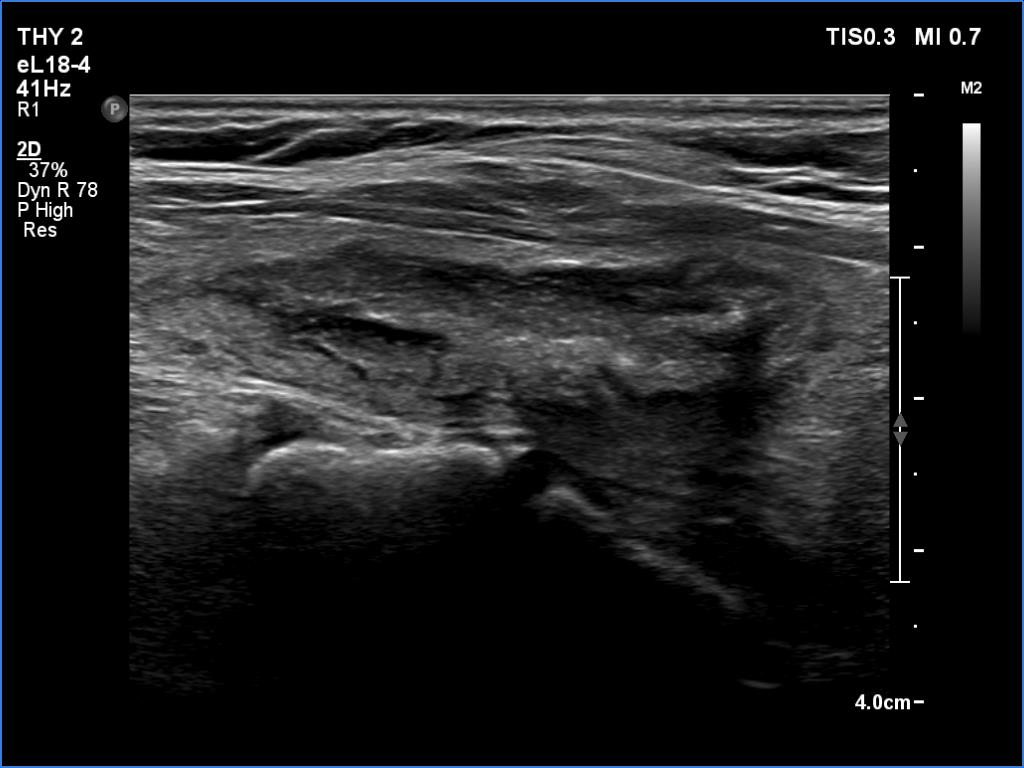

Ultrasonography. The thyroid was echonormal. There were several hypoechoic areas in the right lobe. The left lobe had a large minimally hypoechoic nodule with several tiny cystic areas. The lesion had numerous back wall figures.

In the first part of the ultrasound examination, when the transducer was continuously moving over the thyroid gland, it was not detectable that the contents of the nodule were showing flow. When we stopped the transducer, it became clear that the seemingly solid mass was actually a dense liquid in a continuous flow. On Doppler examination, 'circulation' was visible in continuously changing places.